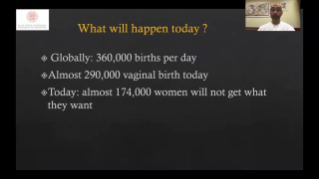

AlimentÊe par la plateforme avancÊe ZST+, la gamme complète de solutions intelligentes Nuewa est con?ue spÊcialement pour amÊliorer la santÊ des femmes avant, pendant et après la grossesse, de manière à poser des diagnostics complets et efficaces pour rÊpondre à des dÊfis cliniques de plus en plus exigeants.